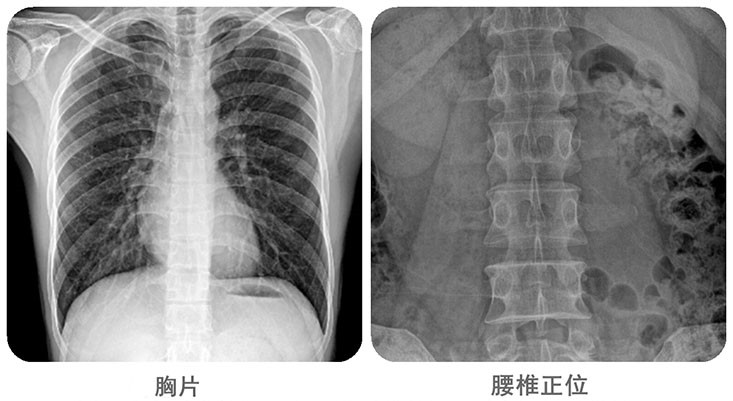

清晰影像,便于臨床診斷。移動(dòng)DR能夠滿足人體的頭部、四肢、胸腔、脊柱、腰椎、腹部等全身多部位的數(shù)字化攝影需求。